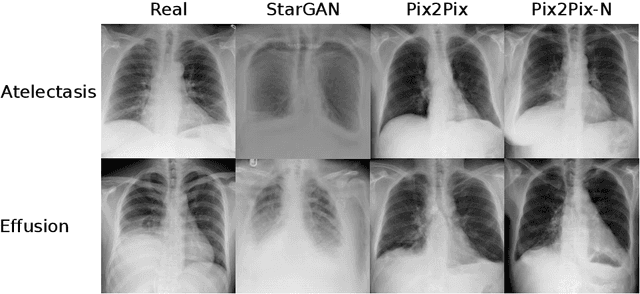

Abstract:Recent works show that Generative Adversarial Networks (GANs) can be successfully applied to chest X-ray data augmentation for lung disease recognition. However, the implausible and distorted pathology features generated from the less than perfect generator may lead to wrong clinical decisions. Why not keep the original pathology region? We proposed a novel approach that allows our generative model to generate high quality plausible images that contain undistorted pathology areas. The main idea is to design a training scheme based on an image-to-image translation network to introduce variations of new lung features around the pathology ground-truth area. Moreover, our model is able to leverage both annotated disease images and unannotated healthy lung images for the purpose of generation. We demonstrate the effectiveness of our model on two tasks: (i) we invite certified radiologists to assess the quality of the generated synthetic images against real and other state-of-the-art generative models, and (ii) data augmentation to improve the performance of disease localisation.